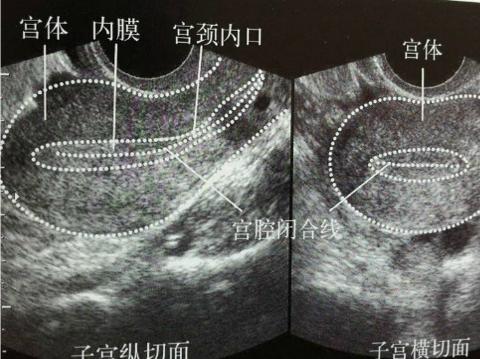

问题1:内膜6mm是否偏薄?经期13天的较大卵泡是15*14,是否长的比较慢?想知道接下来我可以如何增厚内膜?非常感谢您的解答!

首先,卵泡的发育与月经周期的长短有关,并且是一个动态过程。既然是一个动态过程,就不能以一次B超结果为准。以你目前的月经周期天数及B超结果,没有看出有不正常的情况。

其次,内膜的发育与体内激素水平及卵泡发育有关,也是一个动态过程。目前的情况没有特别不好,建议继续观察。

子宫内膜的厚薄和形态,涉及到的是子宫内膜容受性的问题。胚胎着床的成功, 关键在于胚胎发育必须与子宫内膜同步化。所以除了胚胎的质量外, 子宫内膜容受性也起着至关重要的作用。

作为患者,不要纠结于子宫内膜绝对值的厚与薄,不要纠结于子宫内膜一个或两个周期的好与坏。判断子宫内膜,一般有两个标准,即纵向标准和横向标准。横向标准是与临床上所遵守的,公认的正常标准比较;纵向标准是与自己以往治疗周期所比较。对于子宫内膜较薄的患者,经过采取措施,多个周期未达到理想标准,不能作为放弃移植的理由。作为患者,对于如何调整子宫内膜到最佳状态无能为力,有所作为的是调整心态,保持良好的精神面貌,用“顺其自然,为所当为”心情去面对每一个治疗周期。